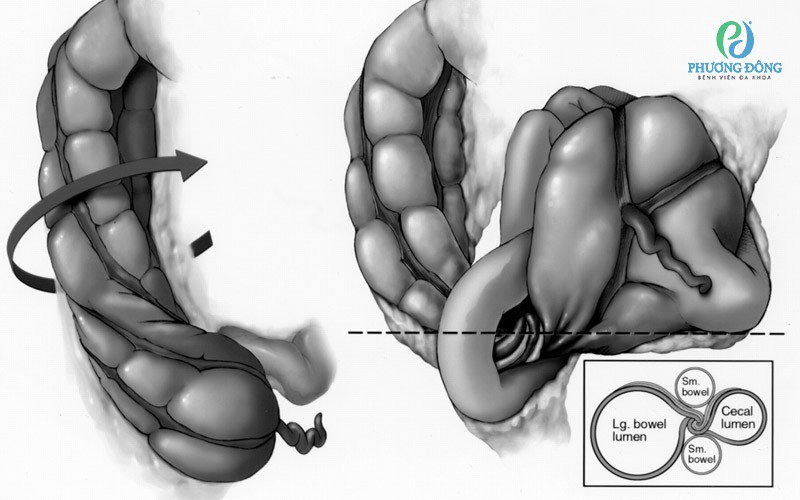

Hình vẽ cho thấy xoắn manh tràng dạng vòng. Hình vẽ cho thấy xoắn manh tràng dạng vòng

Ghi chú: Manh tràng có thể xoắn theo chiều kim đồng hồ hoặc ngược chiều kim đồng hồ rồi lộn ngược lên trên. Đoạn cuối hồi tràng bị xoắn được nhìn thấy bị vướng vào manh tràng. Hình minh họa phía dưới bên trái cho thấy điểm xoắn như trên hình ảnh CT trục. Lg. = lớn, Sm. = nhỏ.